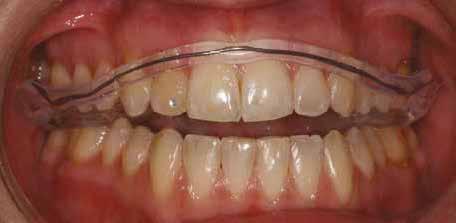

A fogszabályozás aktív fázisa után minden kezelésnél a retenció, a passzív helyben tartó fázis a kezelési eredmény megtartására rendkívül fontos!

Az Essix retainerek, az egy fogívre kiterjedő mélyhúzott sínek, valamint a felső és alsó frontfogakra orálisan ragasztott fix retainerek mellett, a harapás sagittális rögzítésében elengedhetetlen szerepe van az ún. Pitts Izom Tréning Splint-nek, amelybe a páciens élharapásban összeharap, így az megakadályozza az alsó fogsor visszamozdulását a disztálharapásos helyzetbe (13. kép)